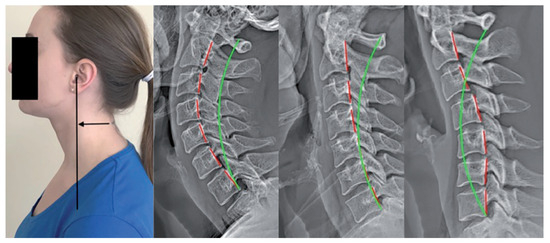

2.2.1. Forward Head Posture (FHP) Assessment with the Craniovertebral Angle (CVA)

2.2.2. Lateral Cervical Radiography: ARA C2–C7 and C2–C7 SVA